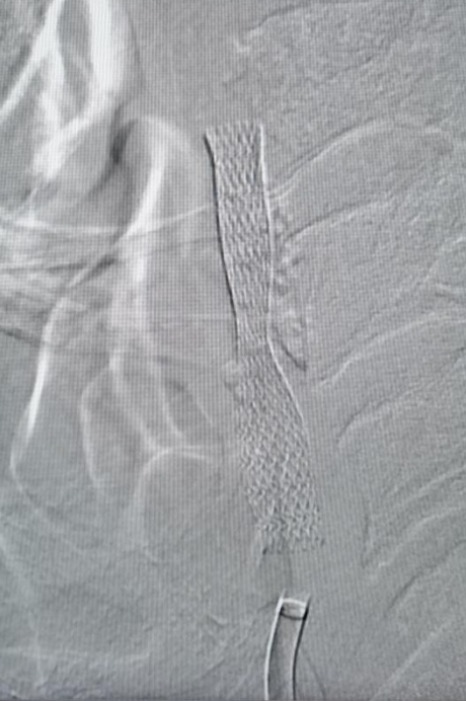

考虑到患者病情复杂、预期手术难度高、风险大,神经内科介入团队根据实际情况,为患者置入了全国首款maurora雷帕霉素药物洗脱支架。术后造影显示,其右侧椎动脉狭窄解除,脑供血不足明显改善,患者恢复良好。据悉,此次椎动脉药物洗脱支架置入术属我院首次开展,成功填补了海南西部地区脑血管介入治疗的空白。

据介绍,与传统金属支架相比,药物洗脱支架通过独特的技术将抑制血管内膜增生的化学药物以涂层的形式附着在金属支架表面,既充分利用了金属支架抗血管回缩能力,又达到了缓慢释放药物长效抑制内膜增生的效果,从而提升了患者管腔的长期通畅率,能防止因血管再次狭窄导致的卒中复发,降低患者二次介入治疗的风险。